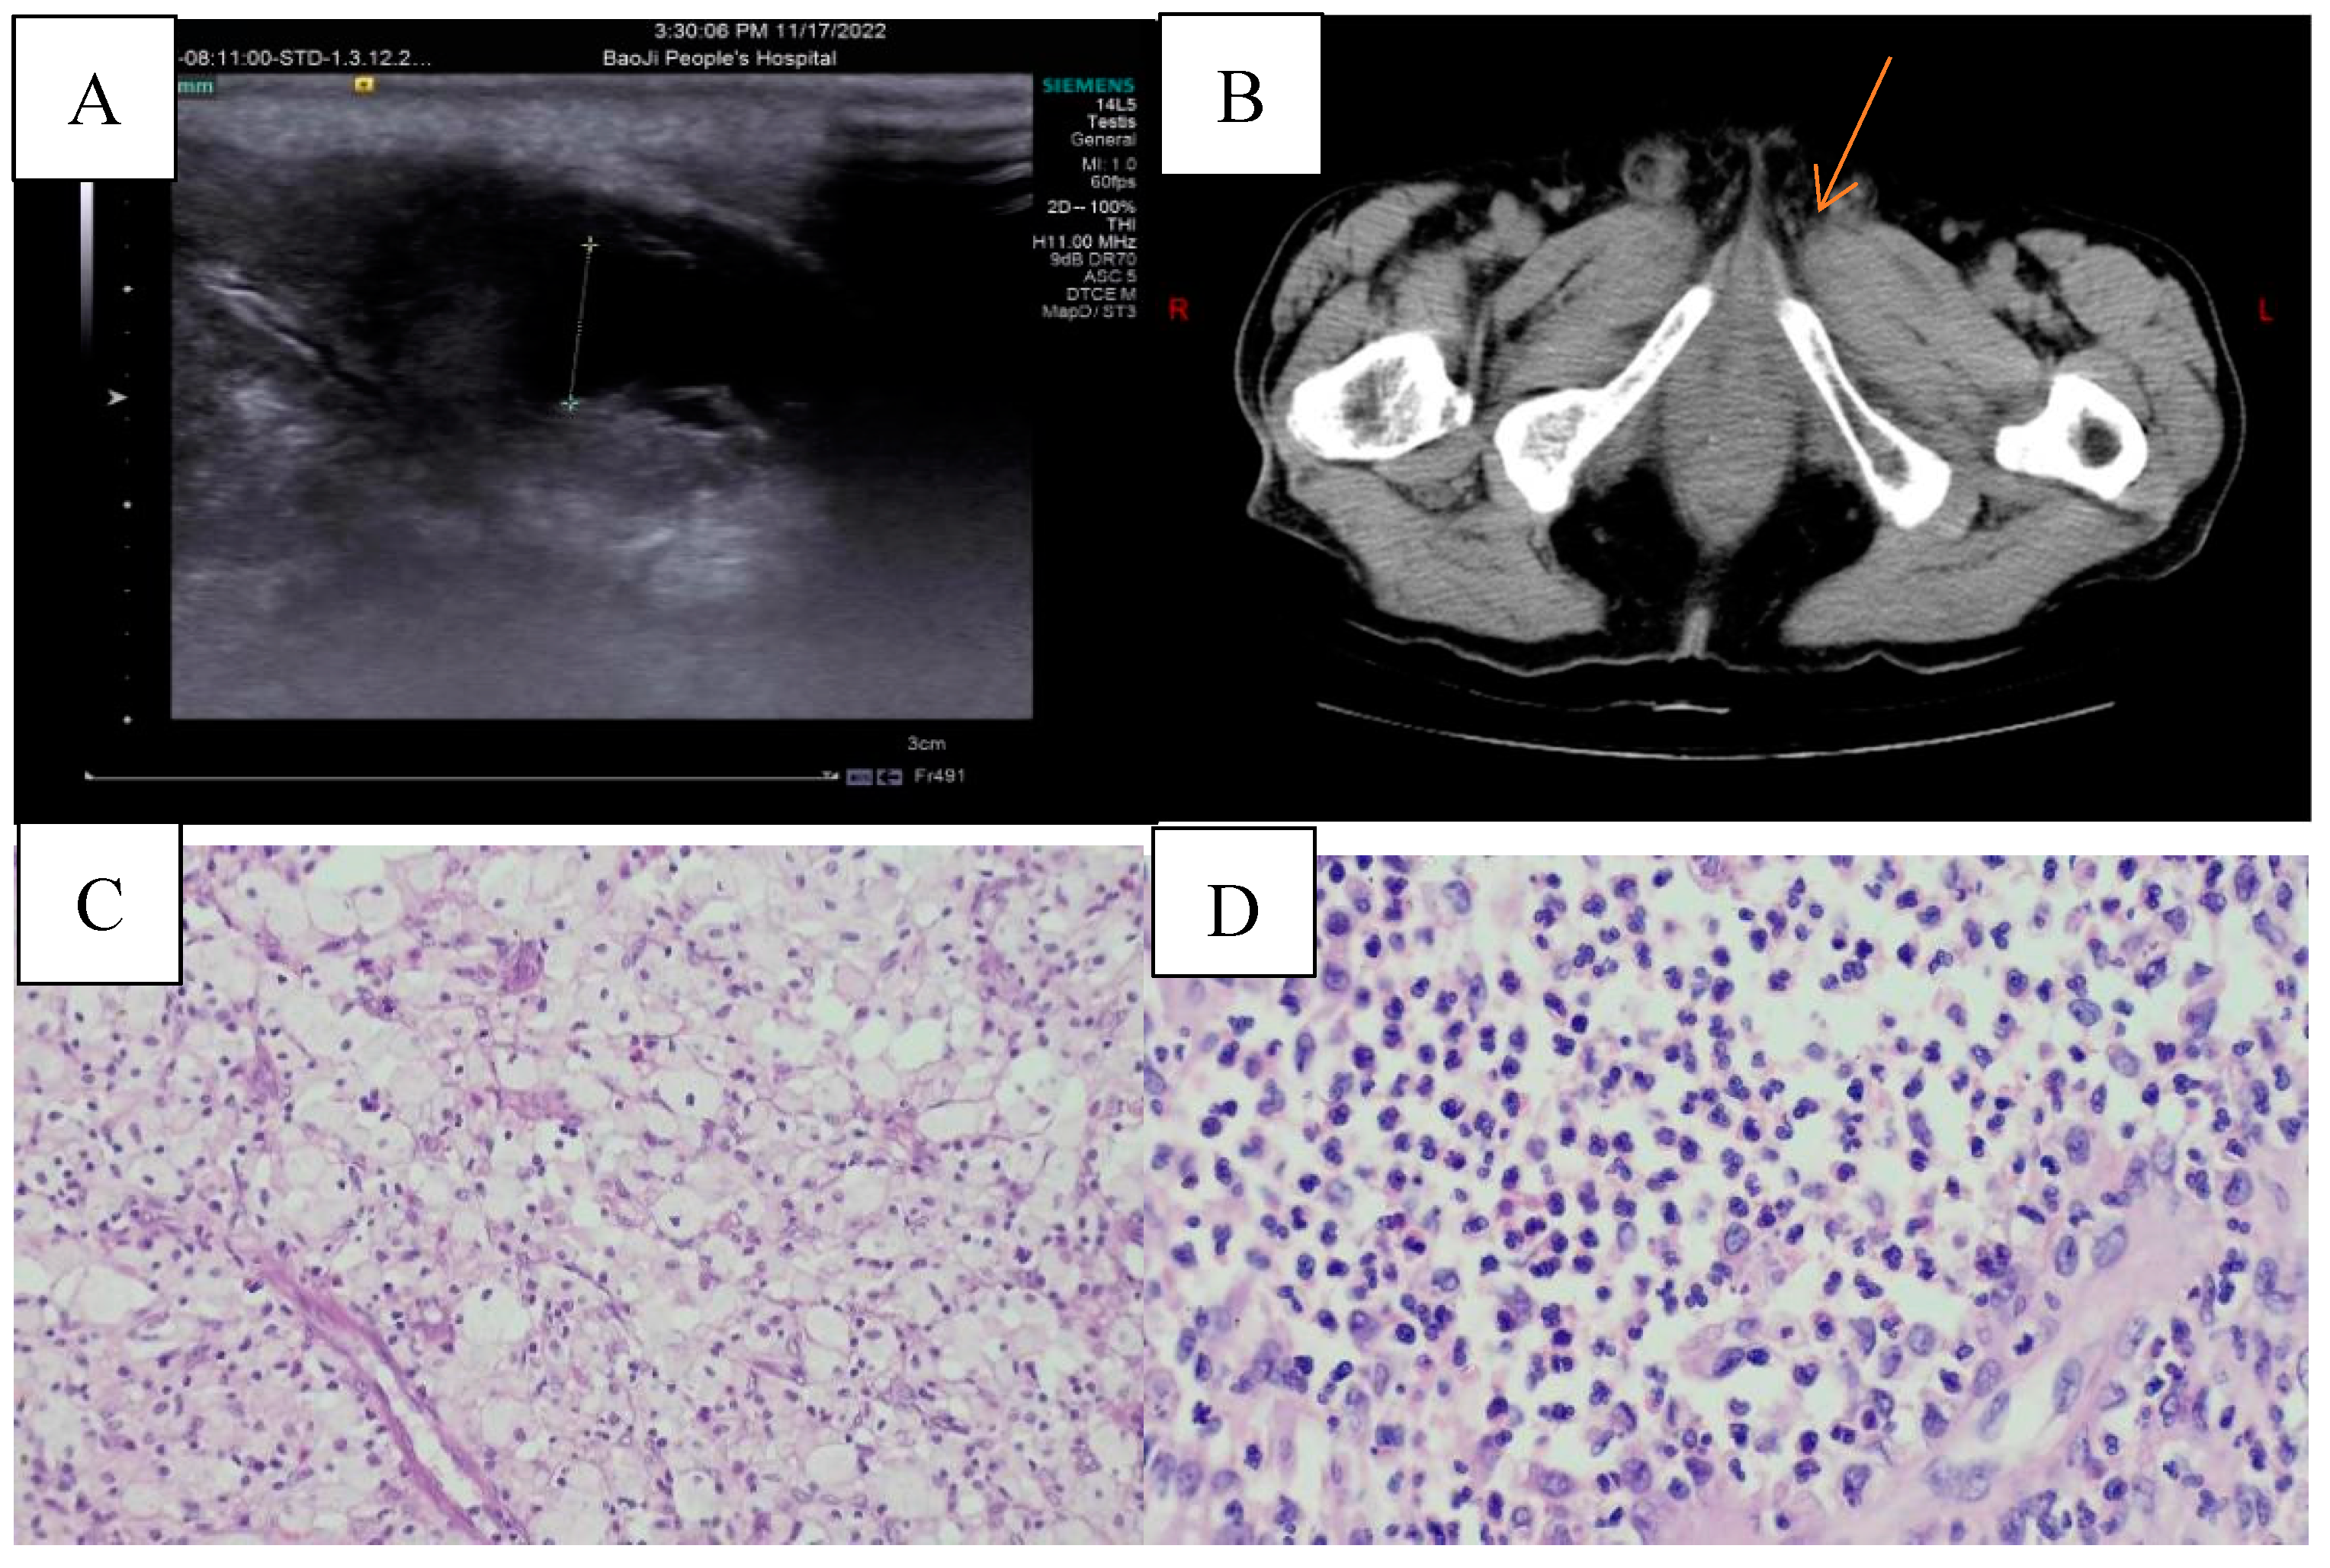

Two weeks ago, a 79-year-old male presented with bilateral scrotal edema and pain accompanied by dysuria. The patient had a medical history of chronic bronchitis and emphysema, and had undergone transurethral resection of the prostate two years prior. During the physical examination, bilateral scrotal enlargement with tenderness was noted, and a digital rectal examination indicated an enlarged prostate degree III, qualitative toughness, and no significant induration. The laboratory examination results show TPSA at 7.30 ng/ml, FPSA at 0.639 ng/ml, carcinoembryonic antigen at 4.35 ng/ml, alpha-fetoprotein at 5.26 ng/ml, testosterone at 12.22 nmol/L, and lactate dehydrogenase at 106 U/L. The urine routine indicates WBC at 2299/ul and RBC at 639.10/ul. No HCG was collected after admission. The scrotal B ultrasound reveals a mixed mass in the left testicle, which could be an inflammatory mass with a small amount of pus. The right testicle is swollen, but no abnormality in color flow was detected. The image in Figure 1A shows a flufluid surround around the right testis. An MRI conducted at a different hospital revealed prostate enlargement that extended upward into the bladder, with a size of approximately 72.2mm x 68.2mm x 76.8mm. A urinary CT scan indicated that the left testis had reduced in volume and had uneven density, while the right testis was enlarged. Inflammatory changes were also observed, as shown in Figure 1B.

After the patient received anti-infection treatment in our department, the desired effect was not achieved. Despite the treatment, the patient's scrotal pain did not show significant relief, and he continued to experience dysuria. After thorough communication with the patient and his family members, we decided to perform a transurethral prostate resection along with bilateral testicular exploration. During the operation, we discovered bilateral partial testicular tissue necrosis with a pungent odor and pus. After careful consideration, we determined that performing a bilateral orchiectomy was the best course of action. Postoperative examination revealed that the left testis had xanthogranulomatous orchitis and local hydrocele changes (Figure 1C), while the right testis had acute suppurative inflammation with bleeding (Figure 1D). Immunohistochemical results showed that CD68 was positive, while PSA and CK7 were negative, and Ki-67 had scattered positivity. Following a 3-month follow-up after surgery, the patient had satisfactory postoperative results and experienced no adverse events.

Figure 1. A scrotal B ultrasound: the mixed mass in the left testicle considers the inflammatory mass and a little pus. Bilateral seminal cord vein internal diameter thickening, echo enhancement, consideration: inflammatory changes. B Urinary tract CT: left testicular atrophy, right testicular swelling, considering inflammatory changes. C Pathological map of granulomatous orchitis (left): sheet distribution of foam tissue cells.(×100). D Pathological map of pyogenic orchitis (right): large amount of neutrophils, small amount of lymphocytes, plasma cells and histiocyte infiltration.(×400).